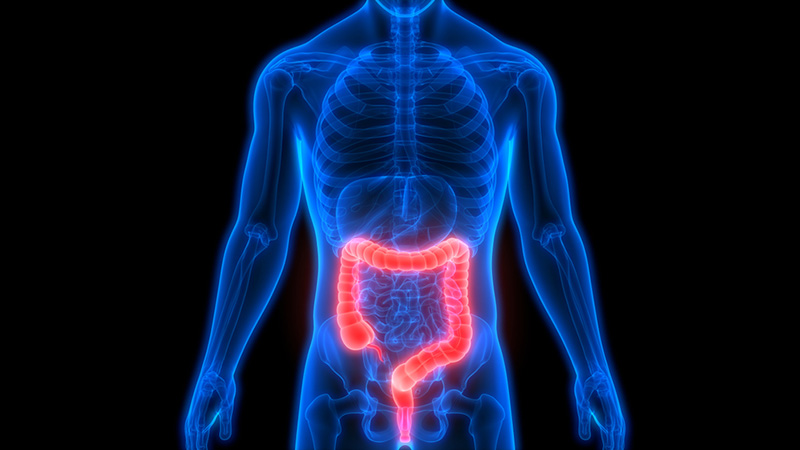

การเลือกหา ดีท็อกซ์ ที่ไหนดี จากวิธีการที่ได้ยินมาโดยขั้นตอนของการชำระสิ่งสกปรกออกจากร่างกายโดยผ่านทางการสอดสวนลำไส้ โดยใช้แรงดันน้ำฉีดสวนขึ้นผ่านทางบริเวณลำไส้ใหญ่ ซึ่งวิธีการดังกล่าวเป็นการทำดีท็อกซ์ของเสียออกจากร่างกายวิธีหนึ่งที่ทางการแพทย์ส่วนใหญ่จะมีการเลือกใช้แก้ไขอาการของผู้มีความรู้สึก ท้องอืด แน่นท้อง ระบบขับถ่ายมีการทำงานที่ผิดปกติ ในปัจจุบันเรื่องของการทำ ดีท็อกซ์ ที่ดีที่สุด มีให้เลือกเข้าใช้บริการผ่านทางสถานที่รับตรวจร่างกาย ในรูปแบบของการดีท็อกซ์สมัยนี้ก็เริ่มที่จะมีการใช้เครื่องมือ เทคนิคของแพทย์ได้ทันสมัยมากขึ้นกว่าเดิมทำให้ความปลอดภัย สามารถมั่นใจได้ในทุกขั้นตอนของการทำ ดีท็อกซ์ลำไส้ ชำระสิ่งตกค้างบริเวณลำไส้ได้รู้สึกโล่งใจกว่าเดิม

ในความเข้าใจของเรื่องการ ดีท็อกซ์ร่างกาย ล้างของเสียที่ส่วนใหญ่แล้วจะชอบนึกถึงเรื่องของการล้วงสวนลำไส้ การล้างโดยแรงดันน้ำที่ขับออกทางบริเวณปลายท่อที่สอดเข้าไปในลำไส้ เพื่อให้น้ำที่สวนเข้าไปมีการล้างสิ่งสกปรกให้ขับออกมาได้คล่องตัวมากขึ้น ซึ่งในการดีท็อกซ์เป็นวิธีการนำมาใช้สำหรับผู้ป่วยที่มีอาการปวดท้องขั้นรุนแรงหรือผู้ที่ไม่สามารถขับของเสียด้วยตัวเองได้ แต่สำหรับการสวนล้างลำไส้เป็นวิธีการใช้น้ำใส่เข้าผ่านลำไส้เพื่อให้การล้างอุจจาระที่ตกค้างได้ออกมาง่ายขึ้น ในความเข้าใจดังกล่าวที่ทำให้ปัจจุบันนี้คนส่วนใหญ่ก็จะกลายเป็นความคิดที่เหมารวมวิธีการทั้งสองว่าเป็นวิธีการทำ ดีท็อกซ์ลำไส้ เหมือนกันนั้นเอง

อย่างที่ได้เข้าใจกันแล้วว่าเรื่องของการทำ ดีท็อกซ์ โรงพยาบาล ที่ให้บริการนั้นมีขั้นตอนของการสวนล้างสิ่งสกปรกต่าง ๆ ขับออกจากร่างกาย ในวิธีการทำดีท็อกซ์ที่ไม่ว่าจะเป็นการใช้น้ำเปล่า น้ำเกลือแร่ ก็มีวิธีการช่วยล้างสิ่งสกปรกภายในร่างกายให้ออกไป แต่ก็เป็นเพียงการนำสิ่งสกปรกที่ตกค้างอยู่ในลำไส้ออกไปเท่านั้น ซึ่งในแนวทางการรักษาโรคเองก็อาจจะเป็นขั้นตอนรักษาตามอาการของตัวเองที่เป็น ไม่ได้ทำให้โรคหายขาดได้จากการดีท็อกซ์ เพราะการทำดีท็อกซ์ลำไส้ จะช่วยแค่เพียงในเรื่องของการขับสิ่งสกปรกตกค้างภายในลำไส้ออกจากร่างกายก็อาจทำให้ร่างกายบางคนมีความคล่องตัว ขยับได้ง่ายมากขึ้นจากความรู้สึกที่ได้ล้างของเสียตกค้างออกไปจากลำไส้ ร่างกายของเรานั้นเอง

ในขั้นตอนของการ บริการดีท็อกซ์ลำไส้ ที่เป็นหนึ่งในวิธีการได้รับความนิยมจากการทำดีท็อกซ์ช่วยขับสิ่งสกปรกตกค้างภายในลำไส้ออกไปได้อย่างมีประสิทธิมากขึ้น ในความทันสมัยของวิธีการทำดีท็อกซ์ที่ตอนนี้เองก็มีการพัฒนารูปแบบของการเลือกใช้เครื่องมือ การใช้น้ำเกลือที่มีคุณภาพมากขึ้นเพื่อให้การล้างลำไส้ สิ่งสกปรกที่ตกค้างสามารถขับออกง่ายมากขึ้น ส่วนของประโยชน์การทำดีท็อกซ์ โดยรวมแล้วก็จะมีส่วนช่วยในเรื่องดังนี้